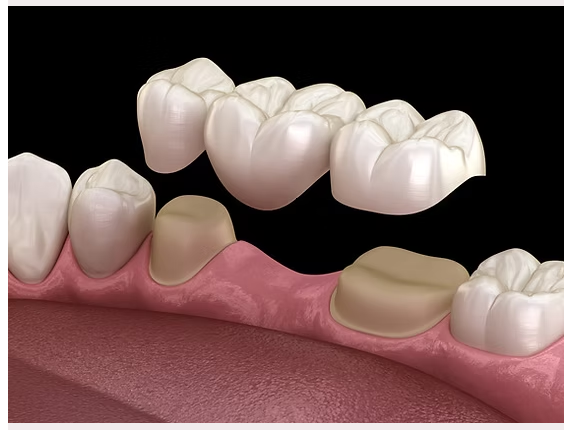

JP Dental Clinic is a leading dental clinic in Koramangala, Bangalore, providing comprehensive dental care with a focus on comfort, precision, and long-term oral health. Our experienced dentists offer advanced treatments including dental implants, root canal treatment, braces and aligners, veneers, teeth whitening, and pediatric dentistry.